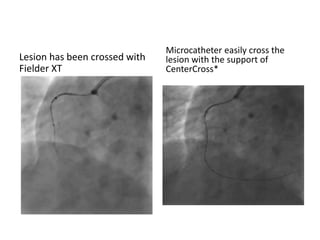

Lesion has been crossed with

Fielder XT

Microcatheter easily cross the

lesion with the support of

CenterCross*